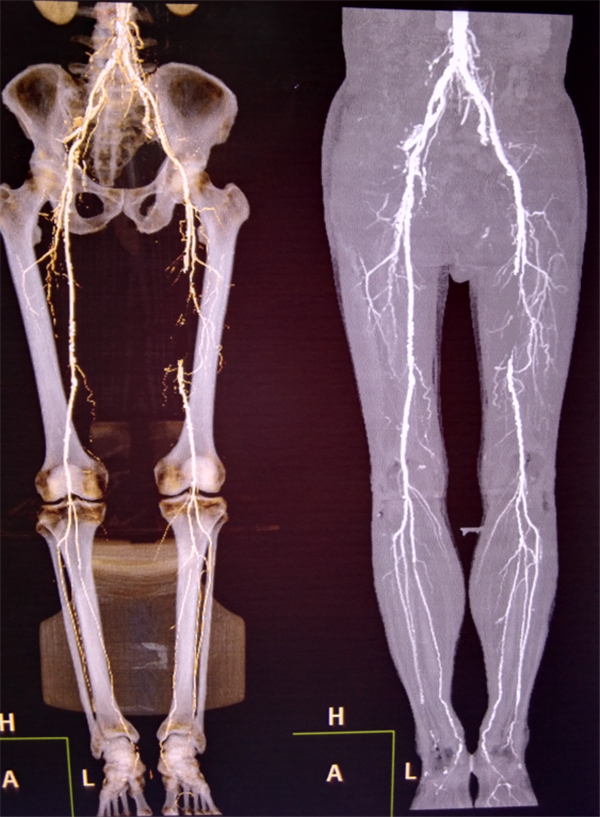

患者周先生,59岁,1年前无明显原因出现双侧小腿及足部发凉,活动后左足疼痛,3月前疼痛加重,出现左足第4及第5足趾发紫,并逐渐进展为足趾发黑、坏死,多处求医用药治疗,效果差,2周前左足疼痛进一步加重,并累及左足第3足趾发黑坏死,无法行走,严重影响了病人的生活质量(见图1)。慕名前来我院血管外科就诊。我院血管外科专家王兵教授为患者制定了详细的诊疗方案,下肢动脉CTA提示患者左侧股浅动脉多发粥样硬化斑块形成,管腔长段闭塞(见图2),明确诊断为“复杂下肢动脉硬化闭塞症”,积极术前准备后,王兵教授带领血管外科崔文军副主任、安乾主治医师、李攀峰医师给患者进行血管腔内介入治疗。术中DSA造影提示:股浅动脉长段闭塞,腘动脉通畅(见图3、图4)。单弯导管配合超滑导丝及微导丝,反复多次尝试顺行开通股浅动脉闭塞段均宣告失败,王兵教授决定采用逆穿技术,在DSA下穿刺腘动脉,成功后逆行置入单弯导管及超滑导丝,顺利开通股浅动脉闭塞段,逆行超滑导丝选入顺行单弯导管内,完成对接(见图5、图6),逆行导丝引出体外,引入球囊扩张股浅动脉闭塞段,股浅动脉闭塞段置入两枚金属裸支架后造影显示左下肢动脉全程通畅(图7、图8)。术后患者胫后动脉搏动恢复,静息性疼痛消失。 复查下肢动脉CTA:左下肢动脉血流通畅(图9)。

图2